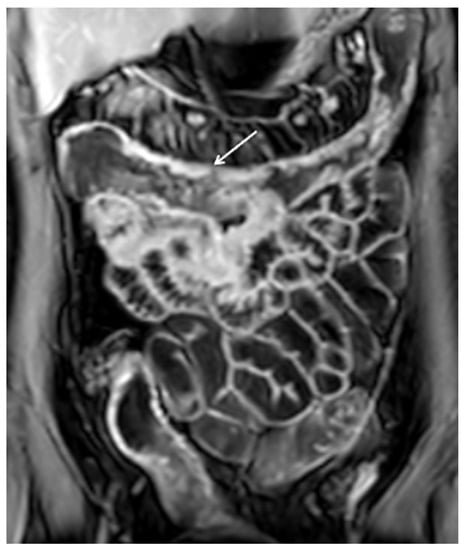

10. Imaging Findings Associated with Active CD Inflammation

| Imaging Findings Associated with Active CD Inflammation |

|---|

Segmental mural hyperenhancement

|

Wall thickening

| Perienteric edema and/or inflammation |

| Engorged vasa recta |

| Fibrofatty proliferation |

| Lymphadenopathy |